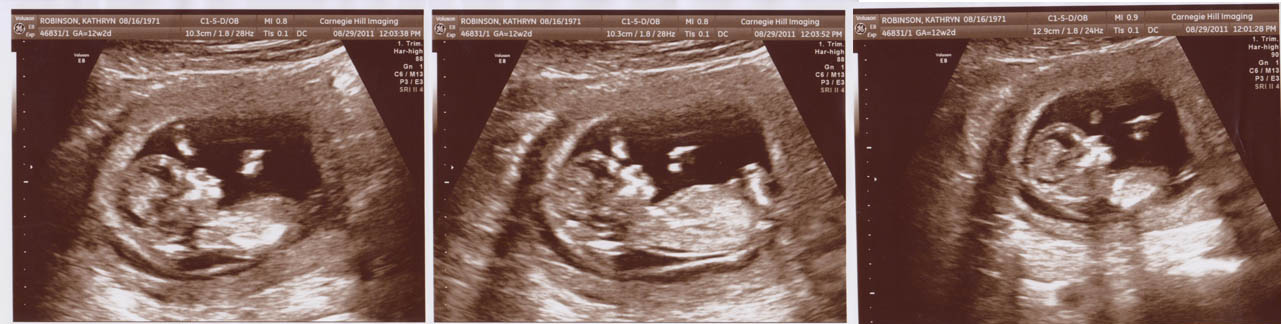

12 Weeks